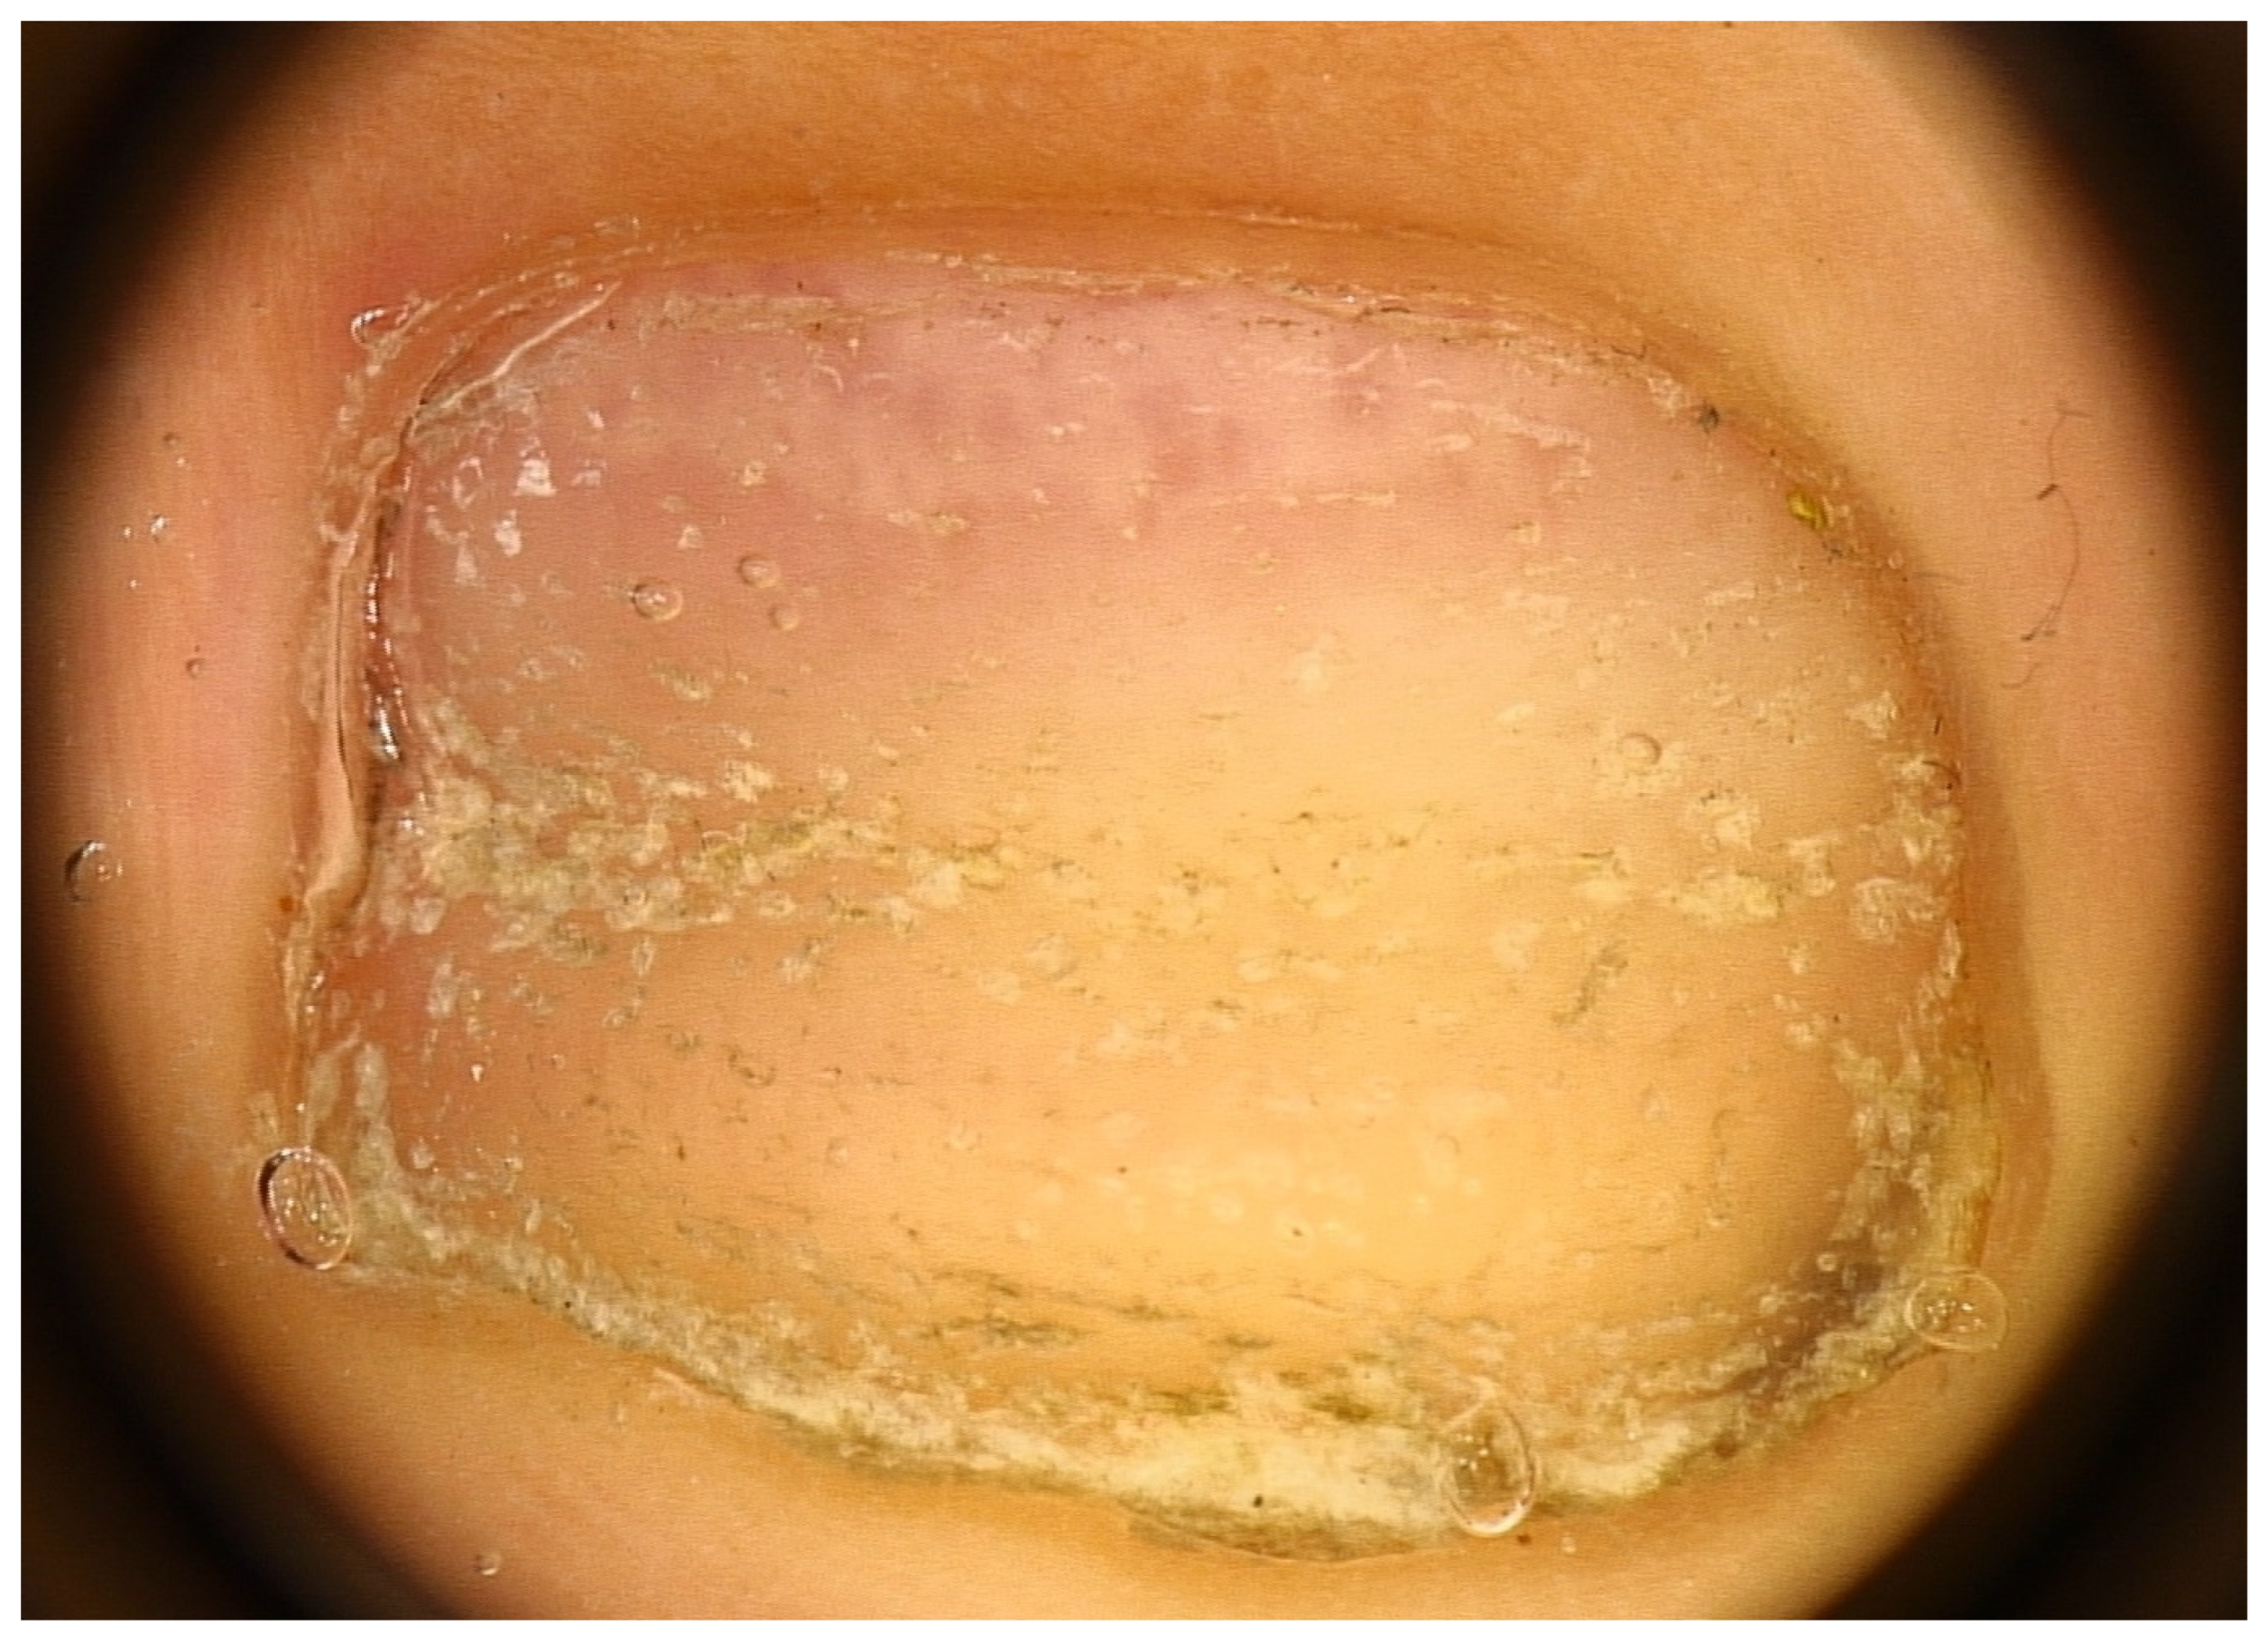

2.2. Trachyonychia